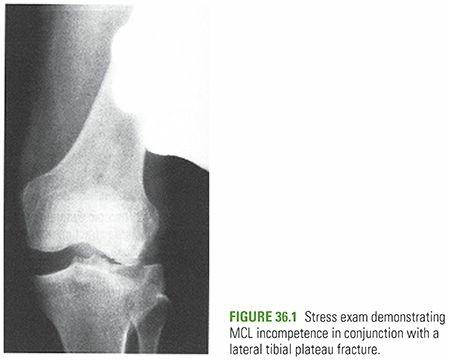

- Joint Instability: Significant instability of the knee joint demonstrated clinically or radiographically, often due to associated ligamentous injury or extensive bony comminution.